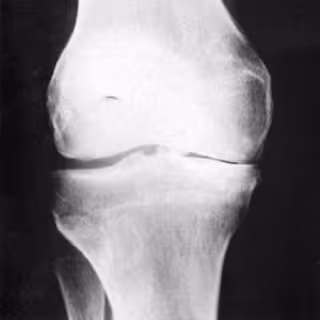

Los investigadores creen que el bloqueo de un estimulador del sistema inmune podría ofrecer protección contra esta pérdida de hueso. A medida que el estrógeno disminuye durante la menopausia, un aumento de la producción de TNF-alpha en la médula ósea activa células que digieren la matriz del hueso, lo que produce osteoporosis. Se desconoce el origen exacto de este TNF-alpha que está producido por varios tipos de células del sistema inmune.